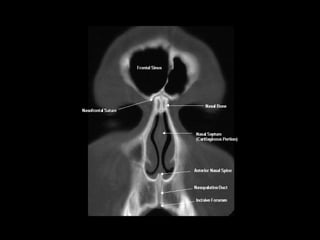

Radiographers use medical imaging equipment like X-rays and MRIs to produce images of patients' internal structures and organs. They are responsible for positioning patients, operating scanning machines, and ensuring quality images. Radiographers must have strong attention to detail, excellent communication skills, and the ability to work well under pressure to accurately capture anatomical features and diagnose any abnormalities.